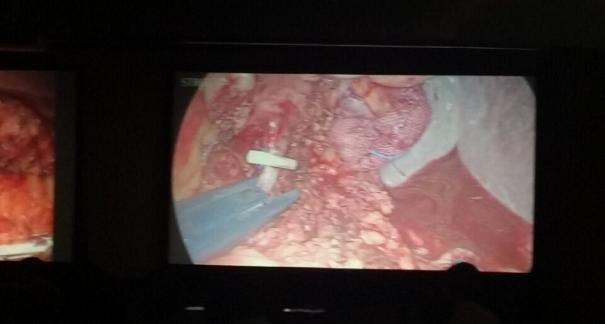

2015年10月23-25日,河北省醫(yī)學(xué)會肝膽外科學(xué)術(shù)年會在河北省石家莊市頤園賓館隆重召開。本次學(xué)術(shù)會議河北省醫(yī)學(xué)會特邀了北京301總院的胡明根教授、天津第一中心醫(yī)院的張雅敏教授、山西醫(yī)大醫(yī)院的趙浩亮、河北醫(yī)科大學(xué)第二醫(yī)院劉建華教授等國內(nèi)知名專家參會。參加會議的醫(yī)院達(dá)100余家,近300名肝膽外科的臨床專家和一線醫(yī)生們親臨會場,在此進(jìn)行廣泛的學(xué)術(shù)交流。25號全天會議安排了五臺手術(shù)視頻演示,全體參會人員進(jìn)行觀摩,并實(shí)時(shí)提問,進(jìn)行手術(shù)交流。演示手術(shù)包括腹腔鏡胰、十二指腸切除術(shù)、腹腔鏡左、右半肝切除術(shù)、腹腔鏡門脈高壓癥的治療、兩鏡或三鏡聯(lián)合膽石癥的治療、開腹胰、十二指腸切除術(shù)、手術(shù)演示中多次使用了我公司產(chǎn)品速豐(可吸收止血結(jié)扎夾),產(chǎn)品使用滿意度受到專家們的一致好評。